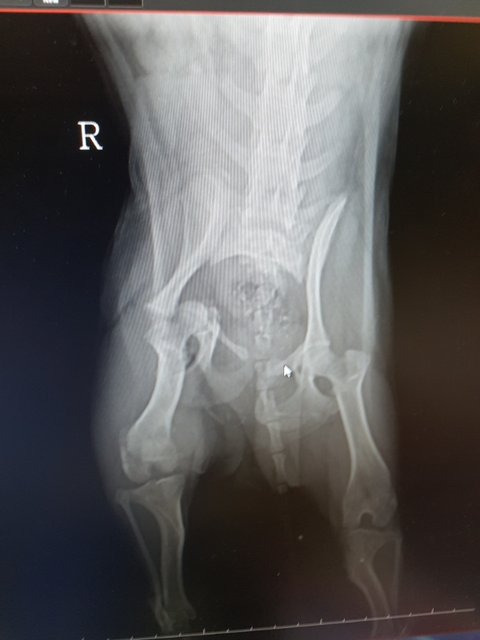

#김제보호소 #교통사고 #뒷다리골반복합골절 #사지말고입양하세요 #유기견입양 #살수있게도와주세요 #치료받을수있게도와주세요

교통사고 당한채로 길에 누워있던 아이라며 시청으로 신고가 들어온 아이입니다

검진을 다녀왔습니다

골반뼈..무릎뼈..복합골절..

다리부분에 피멍이 잔뜩 들어있습니다

여아 1~2살 3.9키로